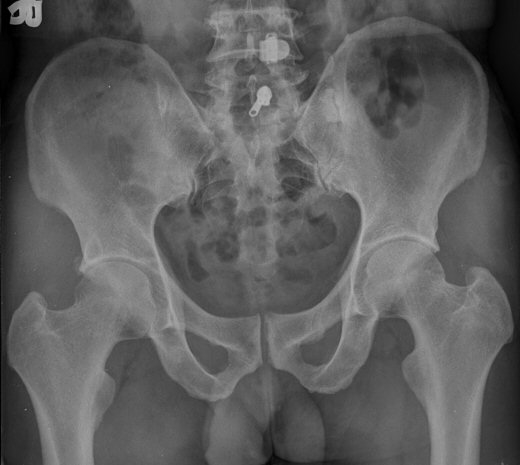

ŽÃËÀÚ¸¦ ¾ûµ¢ÀÌ °üÀý ¿ÜÃø Á¾´Ü¸é°Ë»ç ½Ã ÀüÇÏÀ屨(AIIS)¿¡¼­ ¼®È¸È­¼º À½¿µÀÌ °üÂûµÊ(»çÁø 2, 3).

´Ü¼ø¹æ»ç¼±°Ë»ç

ÃÊÁø ½Ã ½ÃÇàÇÑ ¹æ»ç¼± ÃÔ¿µ»ó ÀüÇÏÀ屨 ºÎÀ§¿¡¼­ ¼®È¸È­ À½¿µÀÌ °üÂûµÇ°í, 3ÁÖ ÈÄ ½ÃÇàÇÑ ÃÔ¿µ¿¡¼­

¼®È¸È­ À½¿µ ¼Ò½ÇÀÌ È®ÀεÊ.